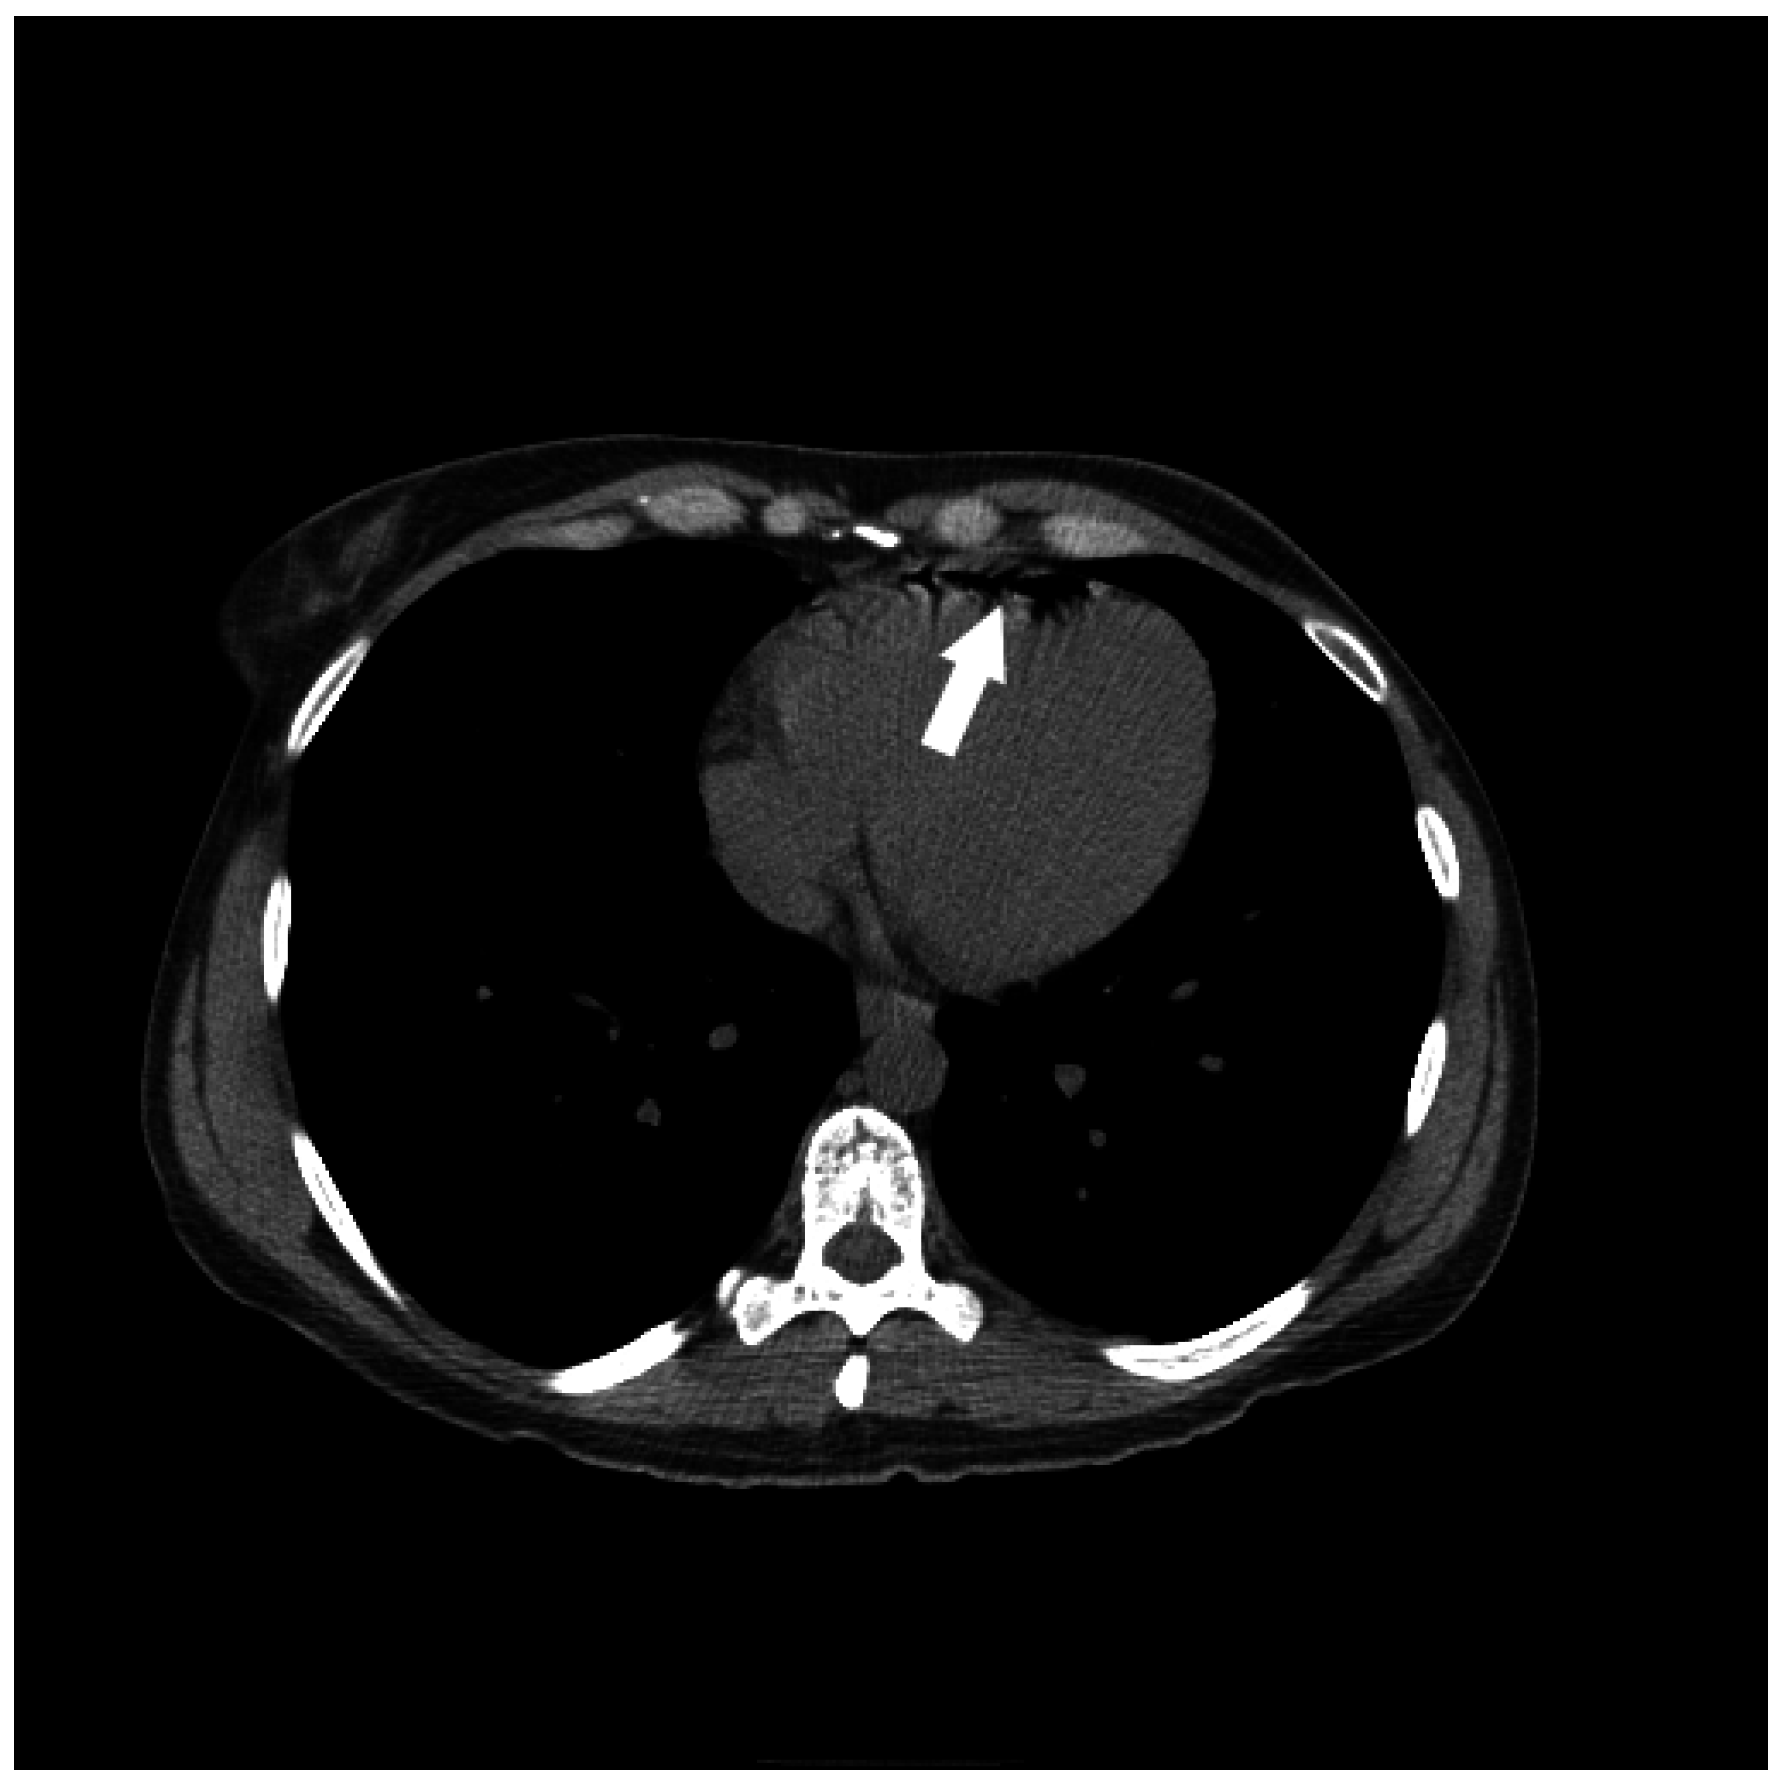

2. Etiology of Air Embolism

3. Clinical Presentation Following Air Embolus

5.1. Initial Management Techniques